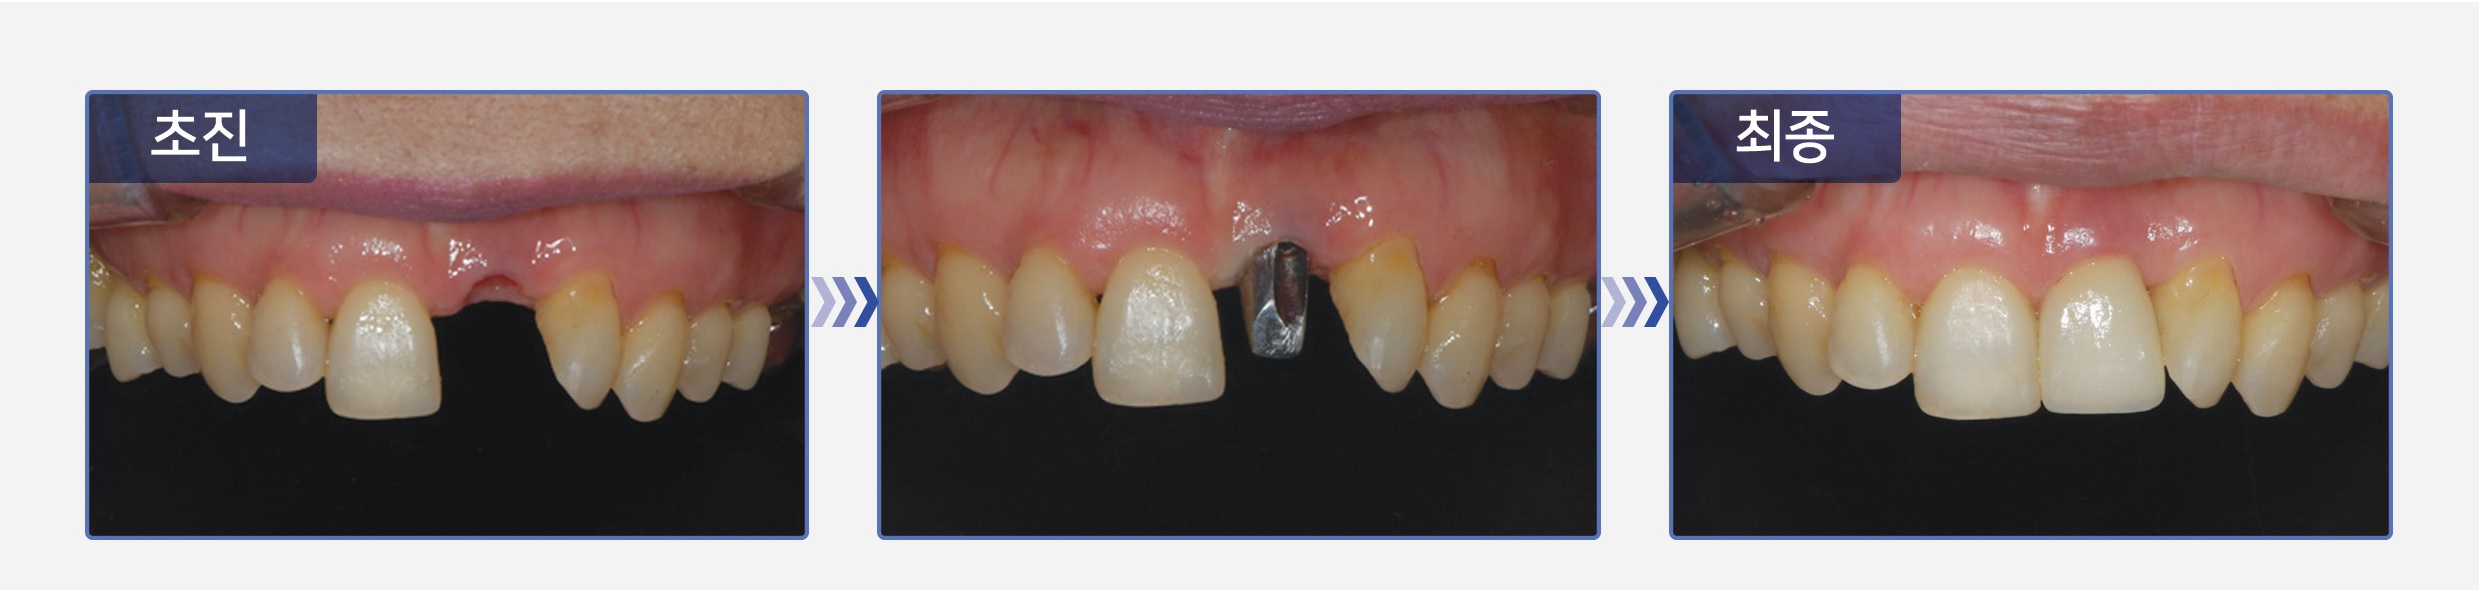

일반적으로 발치에서 임플란트 식립까지 2~3개월 이라는 긴 기간이 필요하지만

서울S에스치과는 많은 경험과 높은 기술력으로 하루 안에 발치와 임플란트 식립을 끝냅니다.

임플란트, 긴 시간을 투자하고 내어달라 하지 않습니다.

“서울S에스치과는 단 하루면 됩니다.”

주변 잇몸 조직의 손상 감소!

치료 단계가 단축되어 전체 치료기간 또한 단축!

회복, 치료기간의 단축으로 빠른 일상 생활 복귀